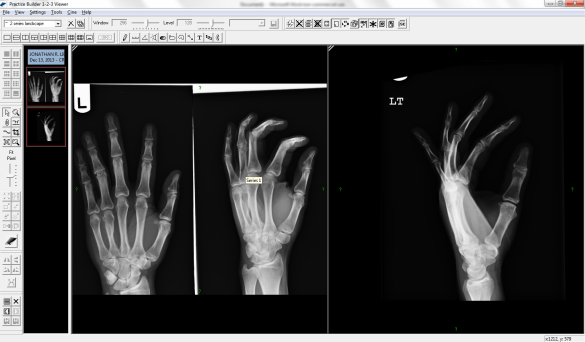

Fast forward to this past fall. In November I have two separate incidents, “sprain” both my hands. I finally go to the doctor. He agrees I probably have a sprain, but will do an x-ray just to add peace of mind. But the x-ray shows a fractured 4th metacarpal in the left had. So off to the bone doctor.

The bone doctor puts the left hand in a cast, and sends the right for an MRI. The x-ray has a shadow he cannot see as a fracture or not. Takes three weeks to get the MRI and back to the doctor around Christmas. I get back, get the cast off the left, but put a cast on the right. Seems it has a fractured scaphoid in the wrist. That cast stays on a month until Monday, where I now have a splint for another two weeks.